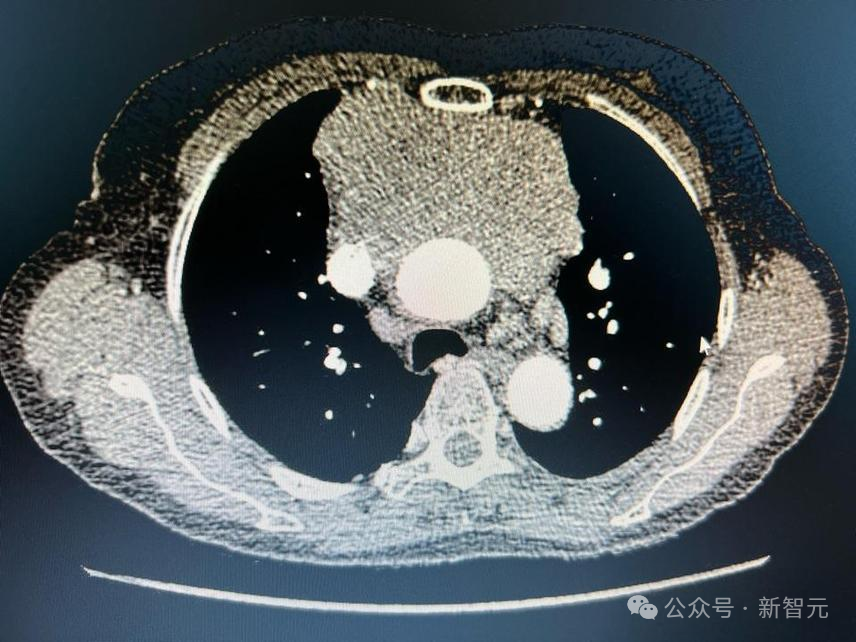

模子留意力得分的可视化表现,CHIEF 正确辨认了玄色素瘤、肺癌和肾癌的癌变地区

模子留意力的可视化表现了肺癌患者生存猜测中的紧张地区